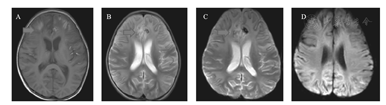

辅助检查:(1)脑电图:入院当日视频脑电图:背景节律减慢(双半球弥漫性2~3 Hz中波幅δ活动为主,夹杂4~6 Hz中波幅θ活动),弥漫性慢波,双额、左颞区尖波、尖慢波、多形性慢波周期性发放,左额为著,清醒期左顶尖波散发,监测到数次临床及临床下电发作。出院时动态脑电图:异常幼儿脑电图(背景活动为弥漫性δ波,睡眠期右侧中央、顶区、左侧顶区棘慢波、尖慢波非同步发放)。(2)头部影像学:入院当天头CT提示颅内出血(图1)。第2天头部MRI符合出血性脑炎表现(图2)。第17天头MRI示双侧额叶、左颞、顶叶弥漫病变,脑炎恢复期改变,左脑额叶脑出血范围较前缩小。弥散成像未见确切异常(图3)。(3)其他:双耳客观听阈检查正常,脑干听觉诱发电位正常,肝胆脾超声正常,双眼闪光视觉诱发电位正常。

A、B:双侧额叶及左侧颞、顶叶脑沟内多发斑片状短T1长T2信号,原左侧额叶小斑片样高T1低T2信号影范围较前缩小。C、D:DWI图示原弥散受限高信号未见显示,相应位置呈低信号,相应表观弥散系数图未见异常低信号征象。

EB病毒脑炎的预后是多变的,有的患者在没有干预的情况下也可以完全恢复,但大部分患者可遗留神经系统后遗症:认知障碍、局灶性神经缺陷或是死亡。特别是存在基底节及丘脑病变的患儿易遗留癫痫或肢体活动障碍等后遗症。本例患儿头MRI进展迅速,在2周后有大面积梗死表现(图3),预后相对较差。